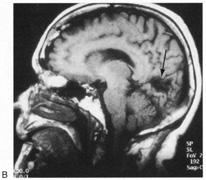

Fig. 15. Bilateral incomplete hemianopia. A 69-year-old man with decreased vision after prostate surgery. A. Fields show remaining central parafoveal vision with some sparing of inferior left quadrant. Note how the defect respects the vertical meridian. B. MRI shows bilateral medial occipital infarction, with sparing of the occipital poles, accounting for the macular-sparing bilaterally. (Courtesy of Dr. Lucia Vaina.)